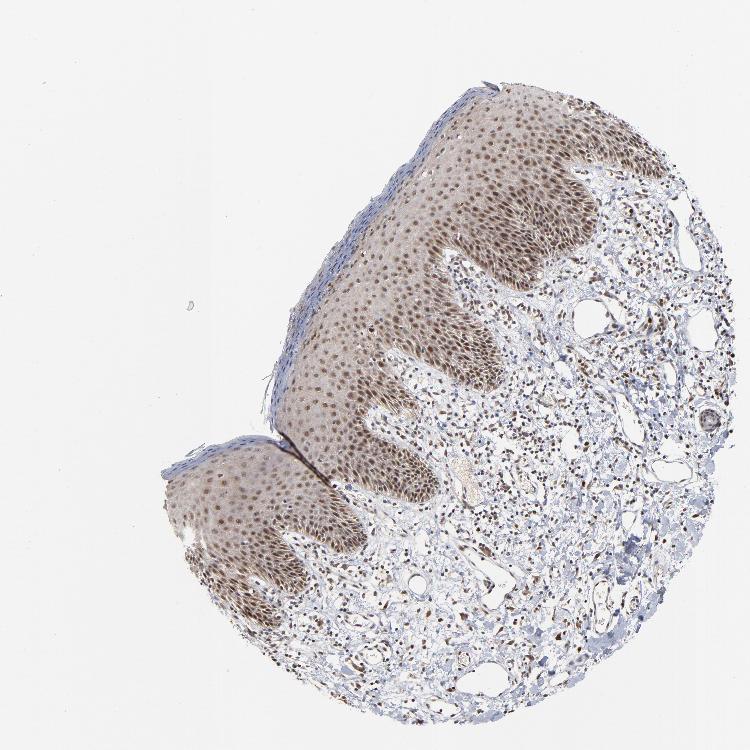

SKIN 1 - Antibody stainingi

Antibody staining in the annotated cell types in the current human tissue is reported as not detected, low, medium, or high, based on conventional immunohistochemistry profiling in selected tissues. This score is based on the combination of the staining intensity and fraction of stained cells.

Each image is clickable and will lead to virtual microscopy that enables deeper exploration of all samples and also displays staining intensity scores, fraction scores and subcellular localization as well as patient and tissue information for each sample.

Antibody HPA003152Antibody HPA003274

Langerhans Not detectedLow

Fibroblasts Not detectedLow

Keratinocytes Not detectedLow

Melanocytes LowMedium

SKIN 2 - Antibody stainingi

Epidermal cells MediumHigh